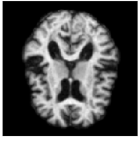

3.4 Similarity of Moment Images

With the method of moments, we seek to maximise the similarity between the moments of the observed data and moments of the stochastic deformation of the initial image I^0subscript^𝐼0\hat{I}_{0}. For an example of the variance of the deformed images and the data sample variance, see Fig. 4. Note that the approximation of the mean I^0ϕ11subscript^𝐼0delimited-⟨⟩superscriptsubscriptitalic-ϕ11\hat{I}_{0}\circ\langle\phi_{1}^{-1}\rangle and the variance Var[I^0ϕ11]Vardelimited-[]subscript^𝐼0superscriptsubscriptitalic-ϕ11\text{Var}[\hat{I}_{0}\circ\phi_{1}^{-1}] are images themselves. Therefore, moment matching turns into matching of images, however not a match of observed images as regularly performed in image registration, but instead a match of I^0ϕ11subscript^𝐼0delimited-⟨⟩superscriptsubscriptitalic-ϕ11\hat{I}_{0}\circ\langle\phi_{1}^{1}\rangle and Var[I^0ϕ11]Vardelimited-[]subscript^𝐼0superscriptsubscriptitalic-ϕ11\text{Var}[\hat{I}_{0}\circ\phi_{1}^{-1}] towards their sample equivalents. Interestingly, we see that classical image similarity measures can be used to compare these images effectively.

The first data sample was simulated based on 9 Gaussian noise fields. The location of the noise fields is shown in Fig. 2, which also shows the initial brain image, I0subscript𝐼0I_{0}. The variation of the simulated data sample is visualized in Fig. 4.

Figure 4: From left: (1.) Pixel-wise variation in the data. (2.) Variation estimated by the model. (3.) Estimates of the variance parameter τk2superscriptsubscript𝜏𝑘2\tau_{k}^{2} compaired to the true values (4.) Estimates of the variance and amplitude parameter compaired to the true values. The length of the arrows correspond to τkλksubscript𝜏𝑘subscript𝜆𝑘\tau_{k}\lambda_{k}. The arrows show the location and width of the noise fields. The red arrows correspond to the true values, while the yellow defines the resulting estimated parameters.

Fig. 4 shows the initial brain, I0subscript𝐼0I_{0}, with a comparison of the true values of τksubscript𝜏𝑘\tau_{k} and λksubscript𝜆𝑘\lambda_{k}, and the values found by the optimisation procedure. The red arrows are the true values, and the yellow defines the estimated parameter values. The model is able to retrieve the parameters of τksubscript𝜏𝑘\tau_{k} for all k=1,,9𝑘19k=1,\ldots,9. It also returns a good estimate of the amplitude parameters, in particular for the noise fields located inside the brain. For noise fields on the boundary of the brain or in the background, the model does not have access to enough information in the intensity differences to return precise estimates of the amplitude parameters.